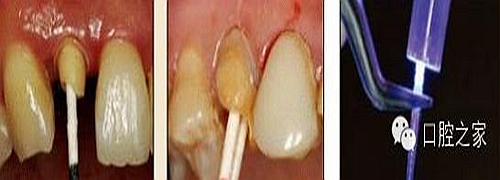

使用全酸蝕粘結(jié)系統(tǒng)粘接纖維樁時,需要應(yīng)用磷酸凝膠對根管進行酸蝕處理,然后再徹底沖洗干凈。根管內(nèi)酸蝕劑的殘留是臨床上經(jīng)常發(fā)生且容易被忽視的問題,也是影響纖維樁粘接的重要因素之一。單獨使用三用槍即使反復(fù)沖洗也很難將根管內(nèi)的酸蝕劑清除干凈,尤其是后牙根管。臨床建議應(yīng)用注射器、三用槍和柱狀毛刷,三者聯(lián)合使用反復(fù)沖洗,以免酸蝕劑殘留于根管內(nèi)(圖 19-1至圖 19-4)。有條件者也可使用超聲波蕩洗根管。

圖19-1:冠部及根管全酸蝕。圖19-2:三用槍沖洗。圖19-3:注射器沖洗。 圖19-4:根管毛刷清洗。